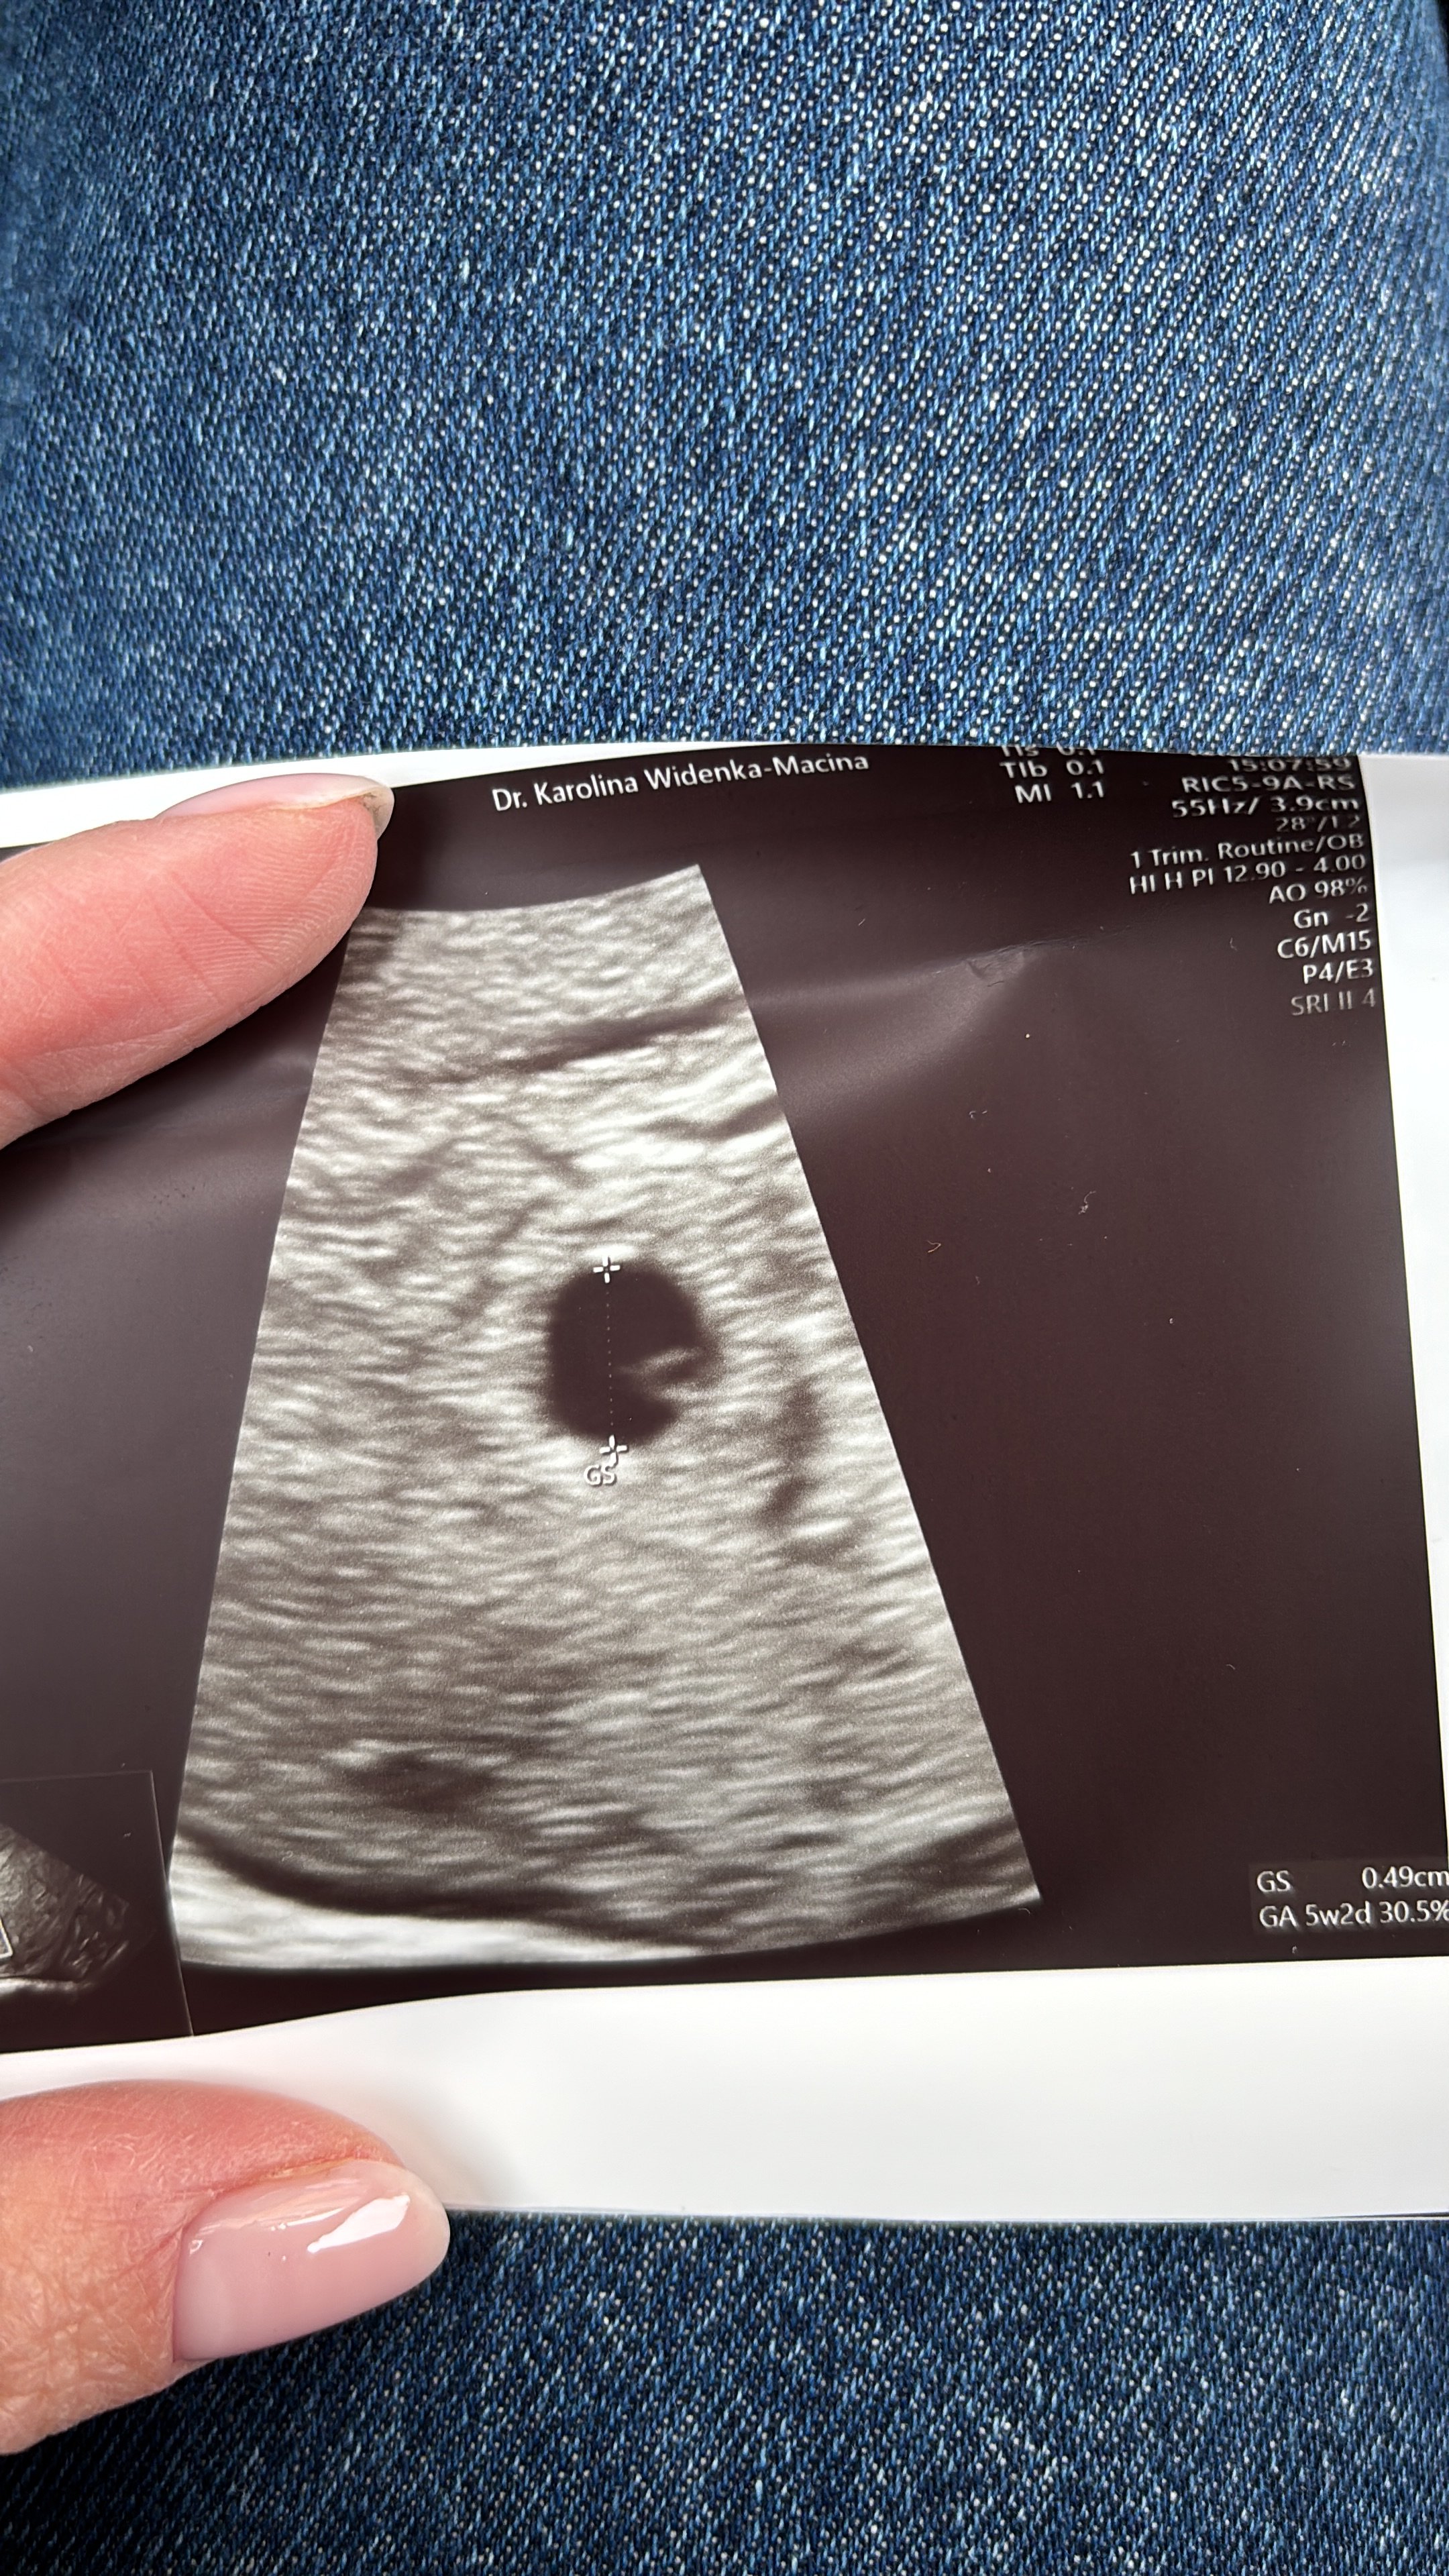

u mnie 5+2Hej dziewczyny, czy to jest odpowiedni widok ten pęcherzyk ciążowy 6,53 mm na 5+2?

5 tydzień 2 dzień Zobacz załącznik 1689112

Jest już chyba pęcherzyk żółtkowy. Tak mi się wydaje nie znam się.u mnie 5+2

Ja myślę że po prostu różnie te komórki się dzieła, sprzęt lepszy - słabszy i już coś widać lub nie...Jest już chyba pęcherzyk żółtkowy. Tak mi się wydaje nie znam się.

Ciekawe czemu u jednych już widać ten pęcherzyk żółtkowy a u innych później. U mnie jeszcze nie widać mimo, że pęcherzyk ciążowy nieco większy. Tak sobie to tłumacze, że może grubsza jestem a szczególnie w okolicach brzucha![]()

moja ginekolog powiedziała, że coś tam było widać, ale nie chce jeszcze nic nazywaćJest już chyba pęcherzyk żółtkowy. Tak mi się wydaje nie znam się.